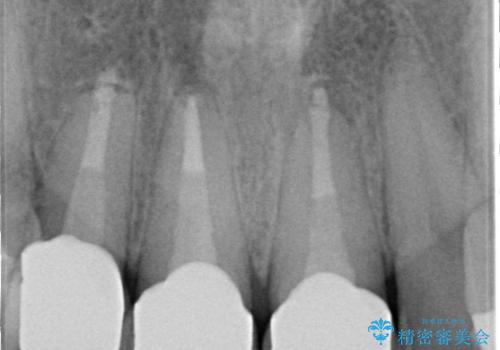

- 昔入れた前歯を綺麗にしたいことを主訴に来院された患者様です。

根尖に病変を認めたため、根管治療を行いセラミッククラウンにて修復を行なっています。

根管充填はMTAにて行なっています。